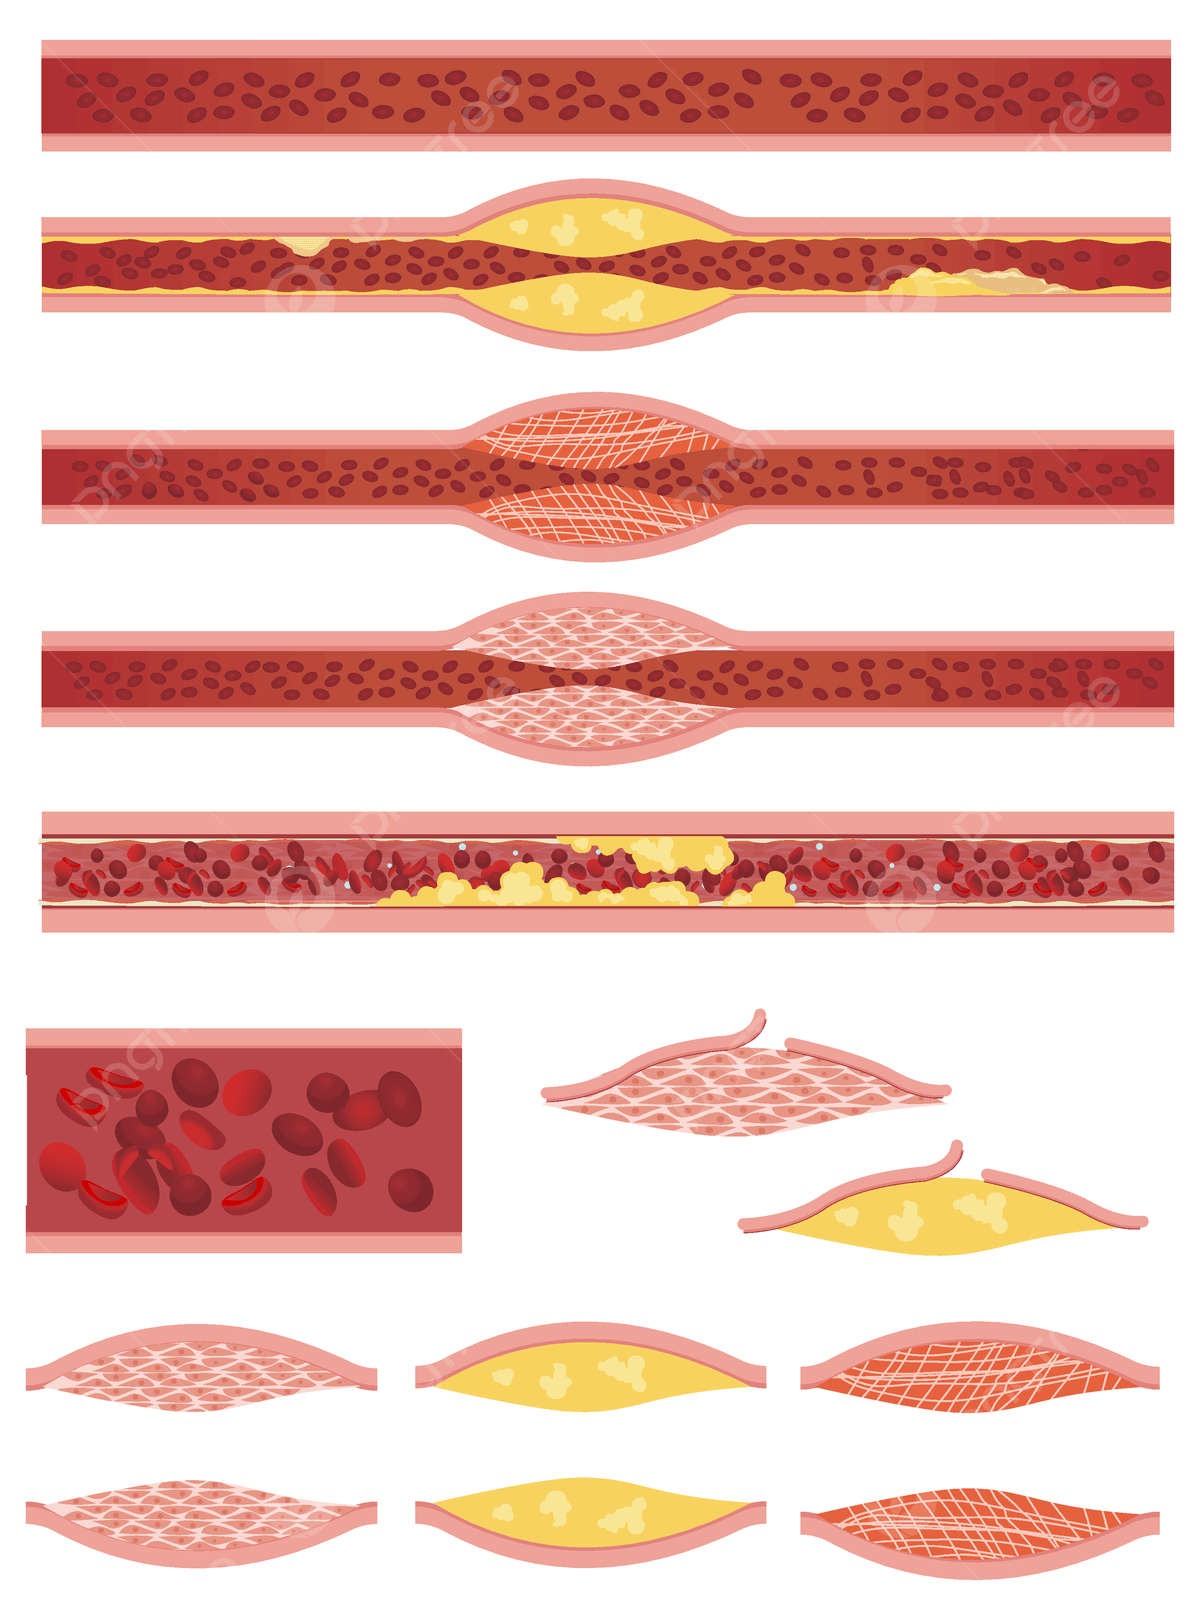

人間の血管の医療静脈血栓の図イラスト画像とPSDフリー素材透過の無料ダウンロード - Pngtree。

血管 詰まるイラスト無料イラスト・フリー素材なら「イラストAC」。

正常な血管と血栓ができた血管 イラスト素材5358451- フォトライブラリ。

動脈硬化、血栓形成。ベクトル医療イラスト。内部の臓器、血栓症、血管内皮のイラスト素材・ベクター Image 61855962。

血栓ができている血管 イラスト素材6665451- フォトライブラリ。